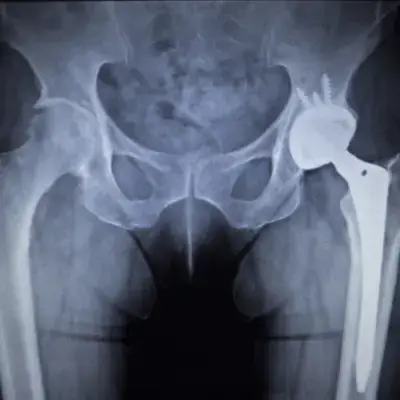

Hip

Hip Diseases and Conditions

As a distinguished orthopedic surgeon, Dr. Pramod Bhor brings a wealth of experience and exceptional skill to the treatment of various hip conditions. His expertise shines when addressing the complexities of issues such as osteoarthritis, hip dysplasia, and femoroacetabular impingement, focusing on comprehensive patient care.

What sets Dr. Bhor apart is not only his extensive knowledge but also his empathetic approach, making him a reliable choice for those in need of hip-related treatment. His ability to connect with patients on a personal level fosters a comfortable and confident environment, crucial for navigating the challenges of orthopedic health issues.

Patients looking for top-notch hip care will find in Dr. Pramod Bhor a dedicated and understanding physician, ready to offer individualized treatment plans that spotlight innovative and effective solutions.

Total Hip Replacement in Navi Mumbai